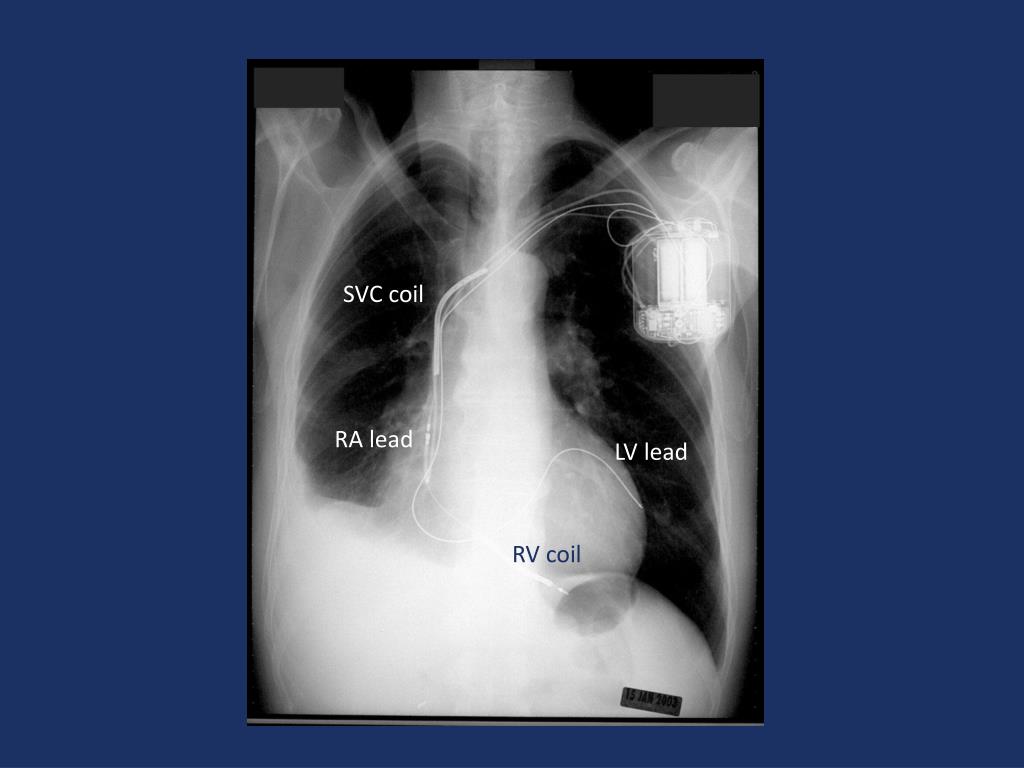

25. SVC coil RA lead LV lead RV coil

26. RA lead LV lead RV lead